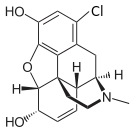

Halogenated morphine derivatives

- 1-Bromocodeine

- 1-Chlorocodeine

- 1-Iodomorphine

Structures

| Other open chain opioids | ||||

|---|---|---|---|---|

1-Bromocodeine |

1-Chlorocodeine |

| ||